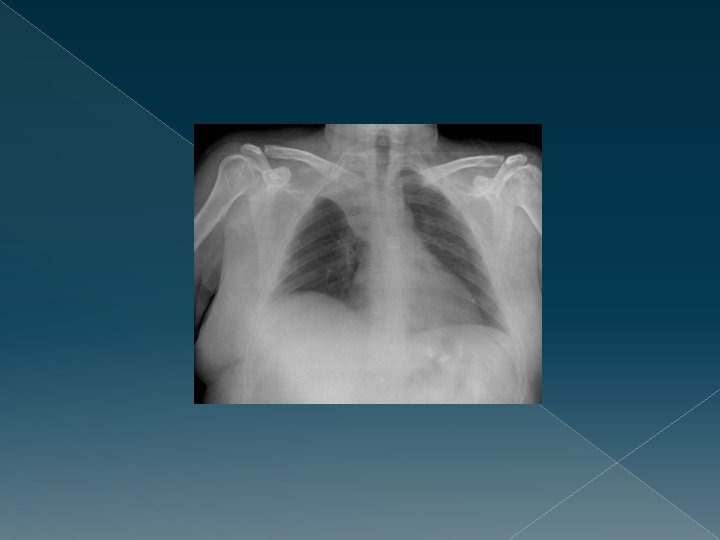

2. Centrada: › Los extremos de las clavículas en la misma altura y equidistantes de las apófisis espinosas. › Hemidiagragmas › Senos costofrénicos. › Cámara gástrica. › Densidad hepática.

3. Bien inspirada: Permite ver bien el pulmón y reduce la magnificación de la silueta cardíaca. Punto más alto del diafragma derecho sobre 7. arco costal. Mal inspirada; Imagen de cardiomegalia, engrosamiento hiliar, ensanchamiento mediastínico.